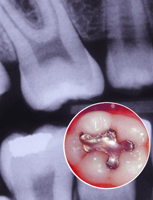

银汞合金补牙对人体有害吗?

本报讯 12月9日,美国生命科学研究所(LSRO)在线发表了“银汞合金对人类健康潜在不良作用的文献分析与评价”的研究报告(http//www.LSRO.ORG/)。研究人员对1996年以来发表的有关文献进行分析后发现,牙填充材料银汞合金除了罕见可引起变态反应外,对人体健康并无危害。

银汞合金是由汞与其他金属(银、铜、锡和锌)组成的合金牙填充材料。它被用作牙洞修复材料已有150多年历史。尽管如此,由于银汞合金中含有汞,所以近一个世纪以来,人们一直担心人体吸入和吸收银汞合金的汞蒸气对健康的潜在危害。很多政府和机构也检验过银汞合金的安全性,结论是科学证据一致证明,人体可吸收银汞合金释放的汞蒸气。尽管如此,由美国卫生部、欧盟执行委员会、世界卫生组织WHO组成的专家小组认为,除了罕见可引起变态反应外,并没有可靠证据证明银汞合金与不良健康影响之间存在因果关系。可是,有些政府仍建议不要给某些病人使用银汞合金。